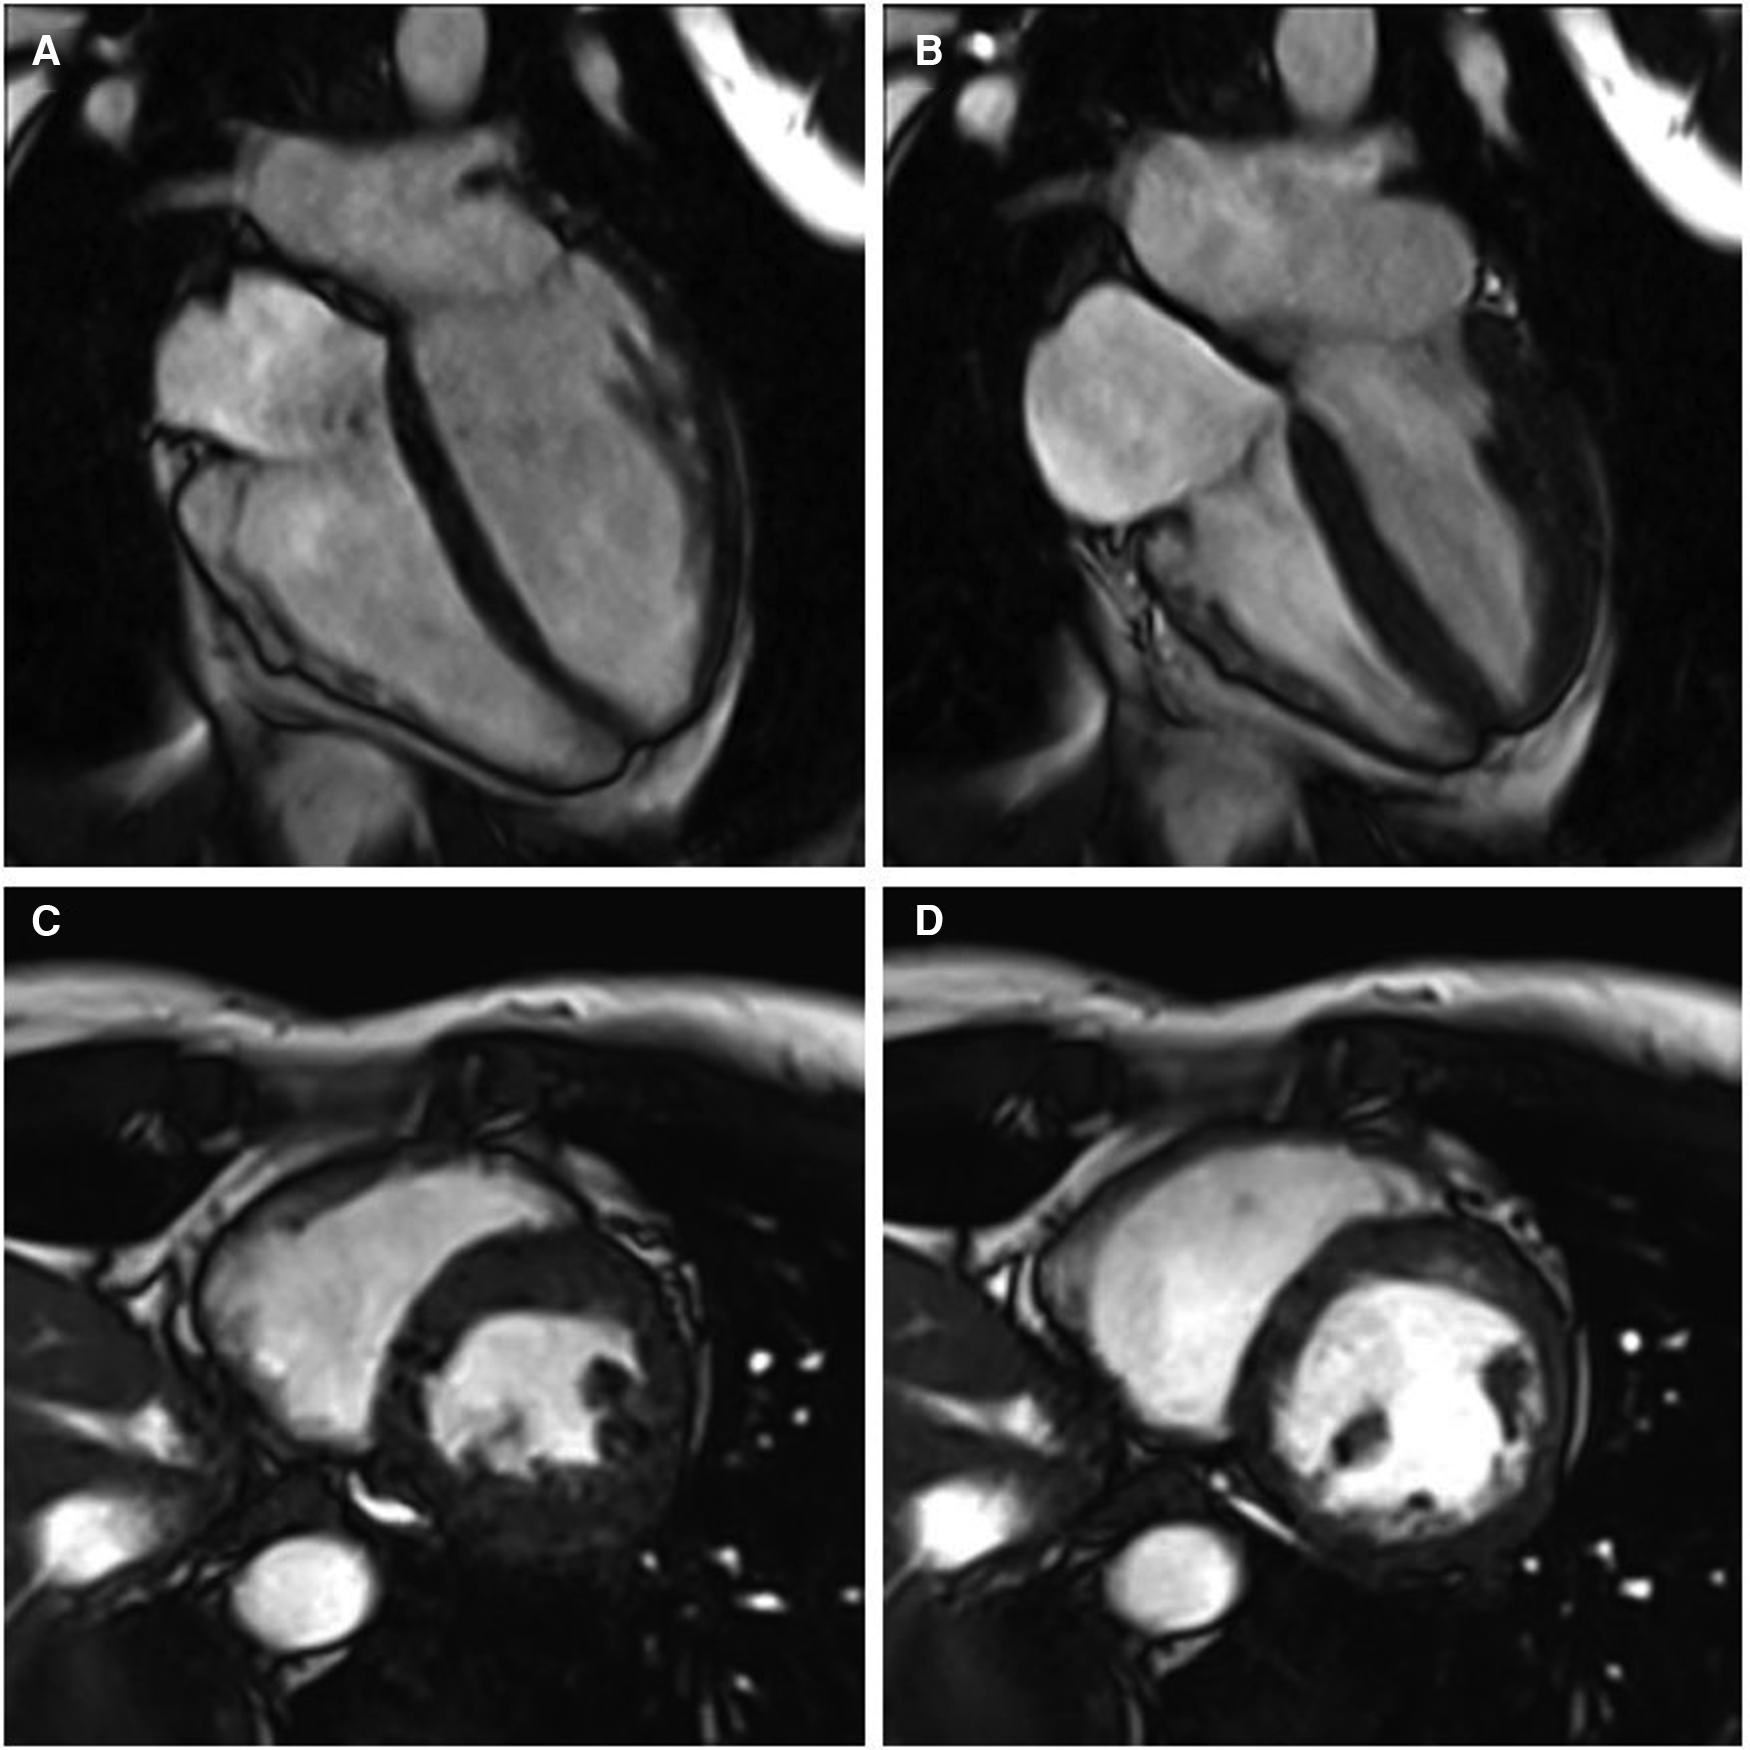

A 41-year-old female with no significant past medical history and no family history of cardiomyopathy or sudden cardiac death was referred for evaluation of persistent frequent premature ventricular contractions (PVCs) following a catheter ablation performed at an outside institution. She was in her usual state of health until a year prior to evaluation, when she developed palpitations, dyspnea on exertion, chest pain, and pre-syncope. The initial evaluation at our institution revealed diffuse low voltage QRS complexes on the 12-lead electrocardiogram, but no inverted T waves or epsilon waves (Figure 1A). A 12-lead Holter monitor showed 28% burden (25,000/24 h) of PVCs with more than 5 different morphologies consistent with RV inflow and outflow tract (RVOT) exits (Figure 1B). A transthoracic echocardiogram revealed normal LV and RV ejection fraction, and normal biventricular dimensions. Cardiac magnetic resonance (CMR) imaging revealed a borderline increased RV chamber size (RV end-diastolic volume indexed for body surface area 107 ml/m2, normal range 51–103 ml/m2) with normal systolic function (RVEF 51%, LVEF 58%) without dyssynchrony, akinesia, or dyskinesia, and no findings suggestive of RV or LV fibrosis, myocarditis, infarction, or late gadolinium enhancement (Figure 2). There were no pertinent findings on physical examination with the exception of occasionally irregular heart sounds due to PVCs.

Figure 2

Cine cardiac magnetic resonance balanced steady state free precession cinegraphic imaging (A) 4-chamber end-diastole, (B) 4-chamber end-systole, (C) short axis end-diastole, and (D) short axis end-systole. Imaging demonstrated mild RV enlargement (RV end-diastolic volume index 107 ml/m2, normal range 51–103 ml/m2) without dyssynchrony, akinesia, or dyskinesia; normal biventricular function (RV EF 51%, LV EF 58%), and no late gadolinium enhancement or other structural abnormality.